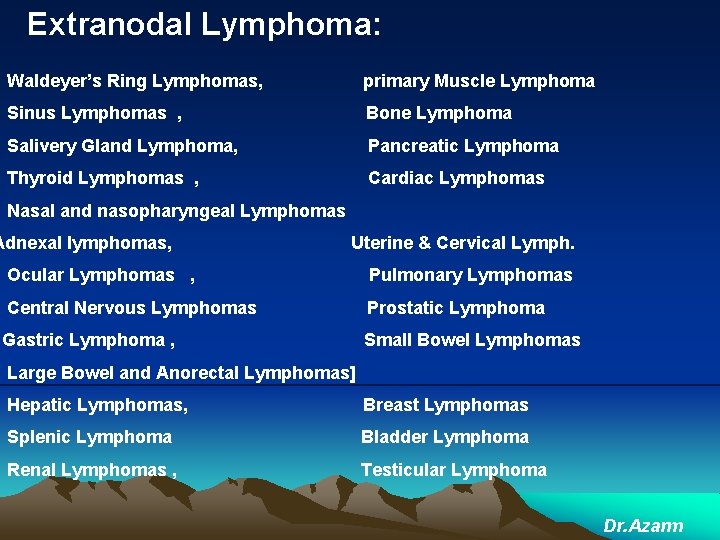

Extranodal Lymphoma: Waldeyer’s Ring Lymphomas, primary Muscle Lymphoma Sinus Lymphomas , Bone Lymphoma Salivery Gland Lymphoma, Pancreatic Lymphoma Thyroid Lymphomas , Cardiac Lymphomas Nasal and nasopharyngeal Lymphomas Adnexal lymphomas, Uterine & Cervical Lymph. Ocular Lymphomas , Pulmonary Lymphomas Central Nervous Lymphomas Prostatic Lymphoma Gastric Lymphoma , Small Bowel Lymphomas Large Bowel and Anorectal Lymphomas] Hepatic Lymphomas, Breast Lymphomas Splenic Lymphoma Bladder Lymphoma Renal Lymphomas , Testicular Lymphoma Dr. Azarm